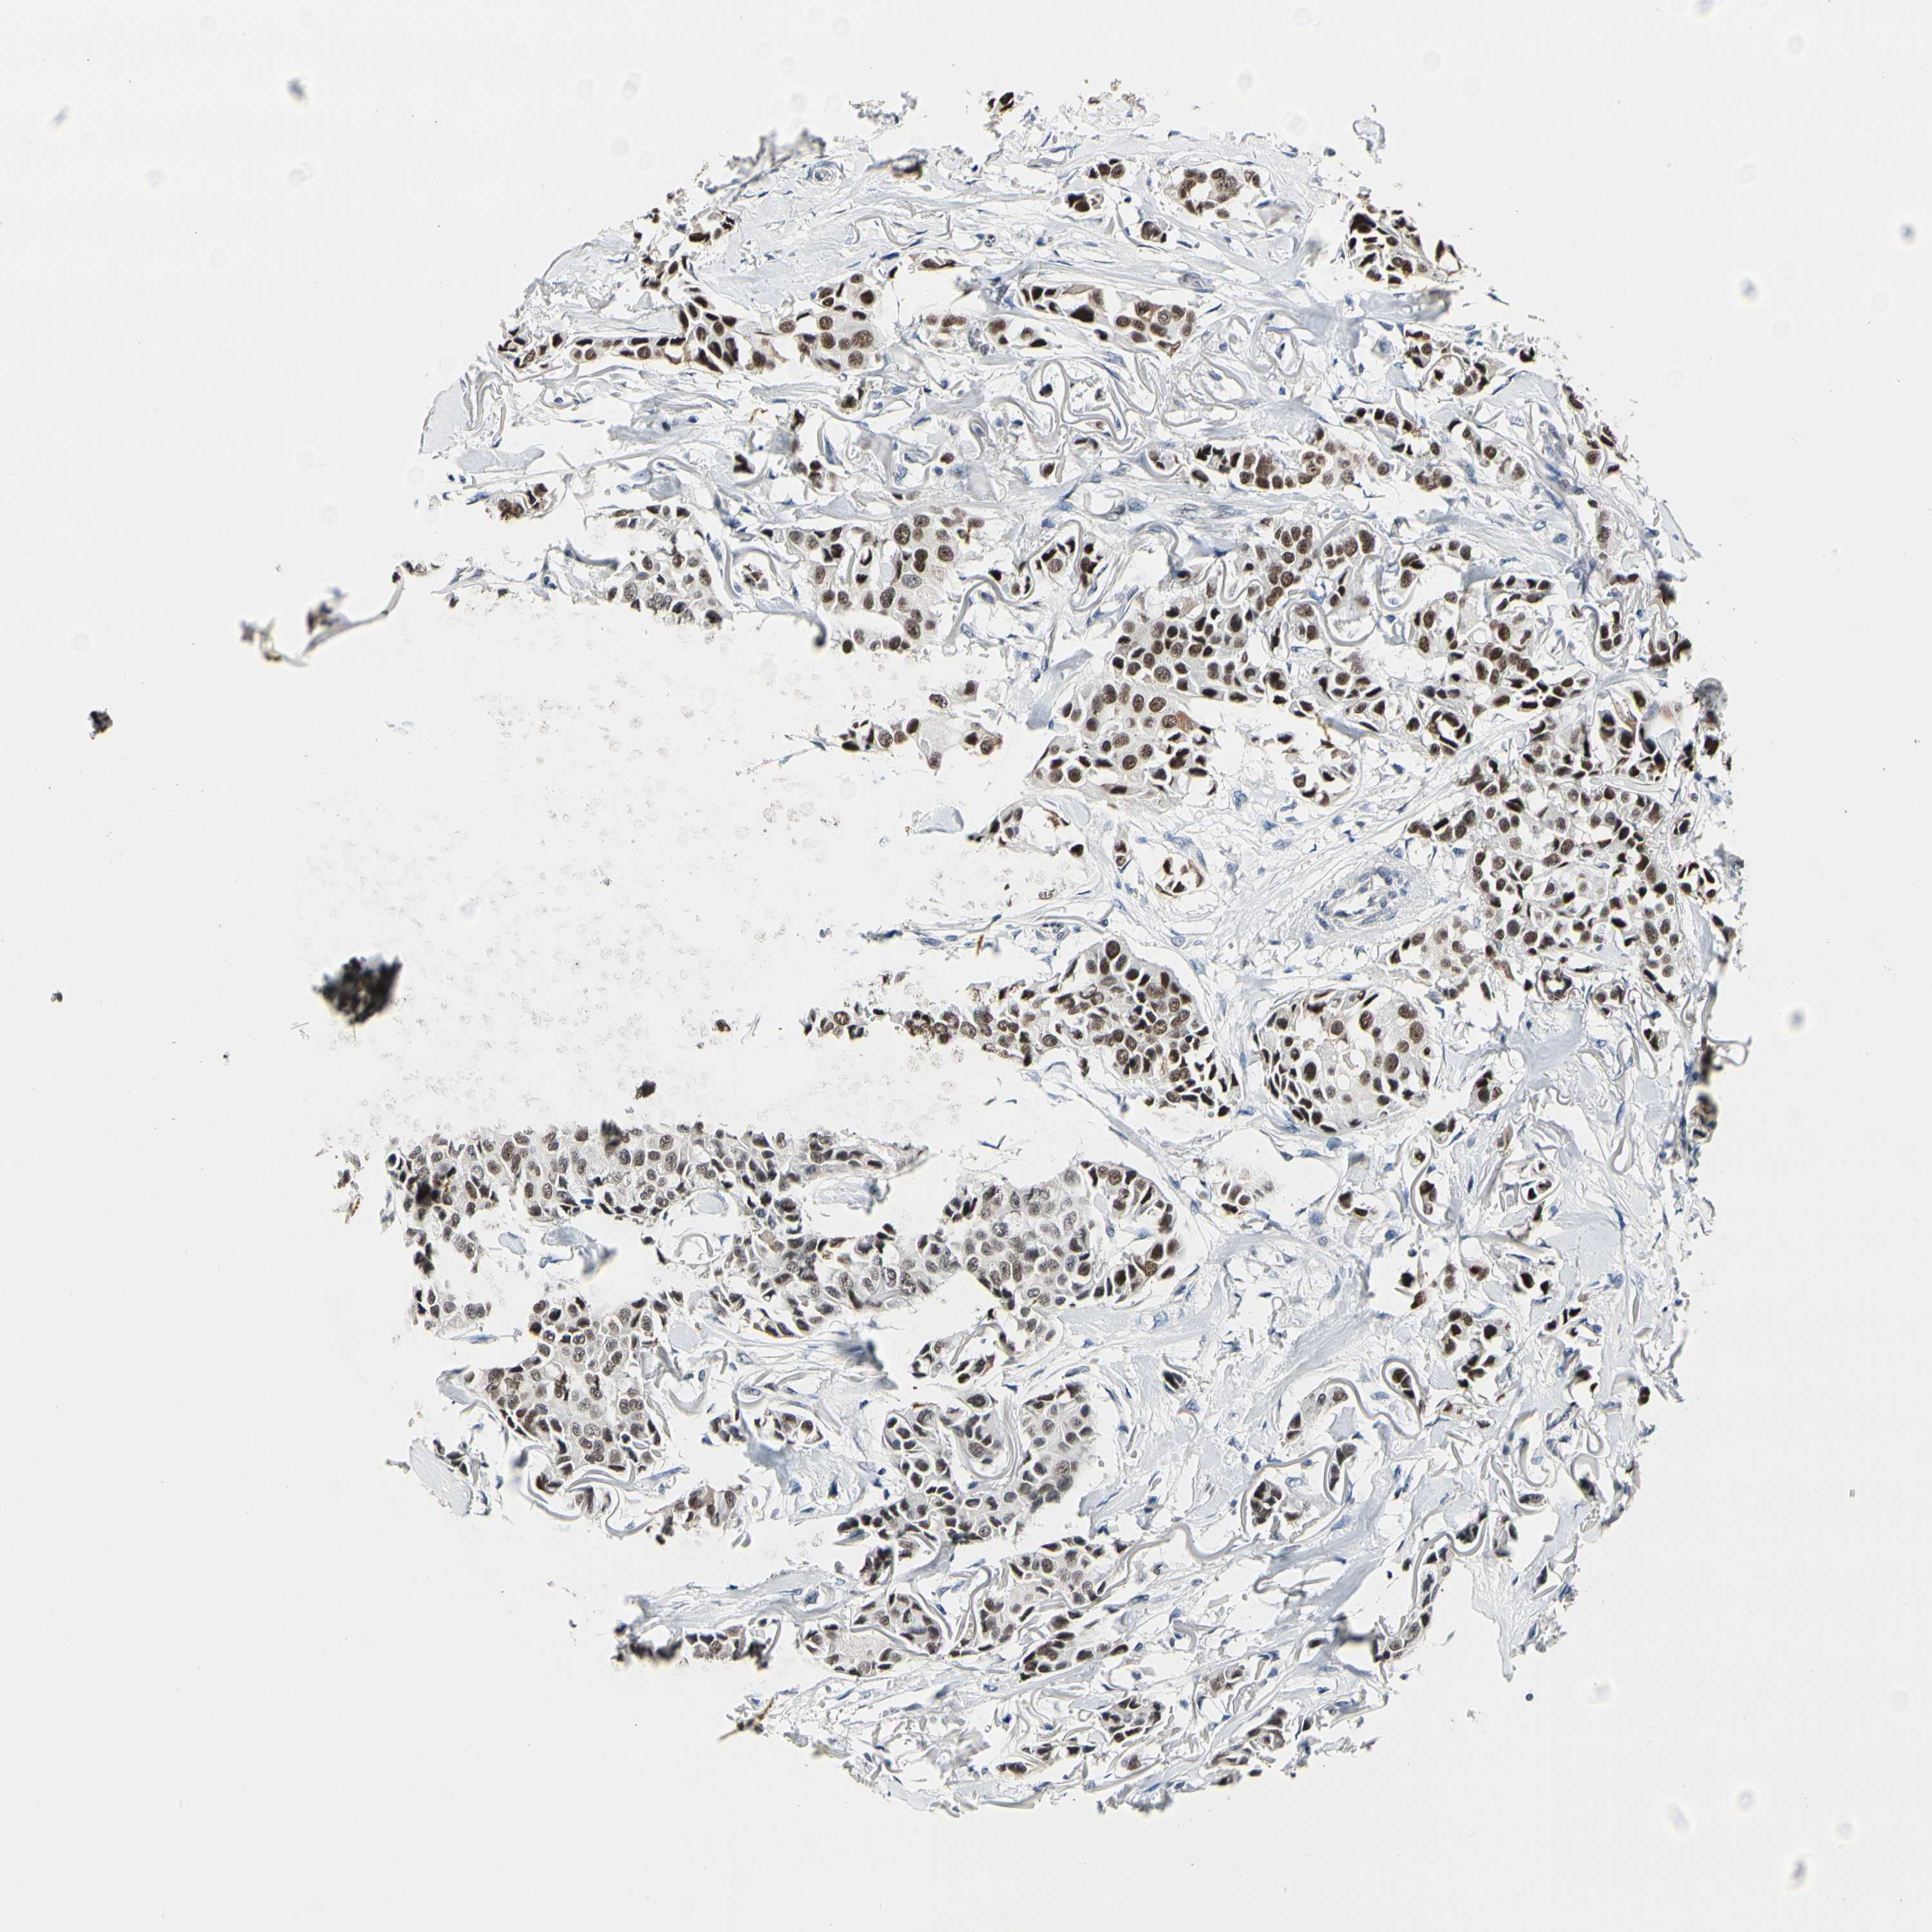

CANCER BREAST CANCER Show tissue menu

BRCA TCGA BRCA VALIDATION PROTEIN EXPRESSION

Breast cancer

Human cancer